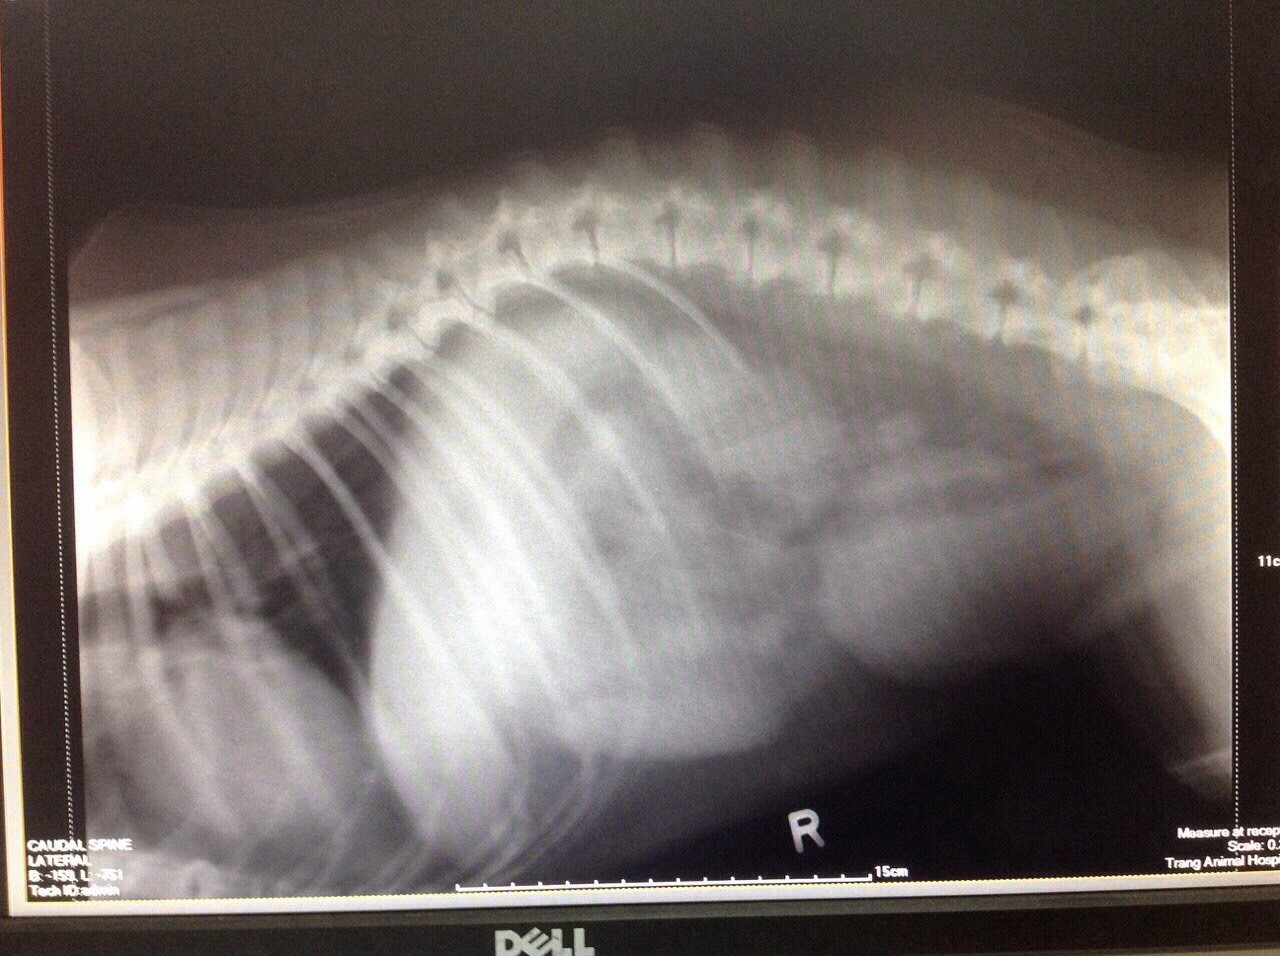

น้องหมาขาหลังไม่มีแรงกระทันหัน พาไปหาหมอตรวจเลือดต่างๆไม่เจออะไรผิดปกติ. หมอฉีดยาแก้ปวด ให้ถึงตอนนี้ยังเดินไม่ได้แต่กินได้ปกติ เป็นหมาไทยอายุ9 ปี หมอสันนิฐานว่ากระดูกทับเส้นผระสาท แต่ยังไม่สามารถสรุปแน่ชัด ตอนนี้เป็นมา 2-3 วันแล้ว มีรูปเอ็กเรย์มาให้ดู ซึ่งก่อนหน้านี้น้องหมาก็เดินวิ่งเล่นได้ปกตือยู่เลย

ตอนนี้หมอแนะนำให้ไปตรวจที่จวฺ สุราษฎรธานี. น้องหมาอยู่ตรัง. ขอคำแนะนำครับ เผื่อมีใครช่วยวิเคราะห์ฟิมเอ็กเรยได้จะได้เป็นข้อมูลเพิ่มเติม หรืออื่นๆ. ก็แนะนำได้ครับ